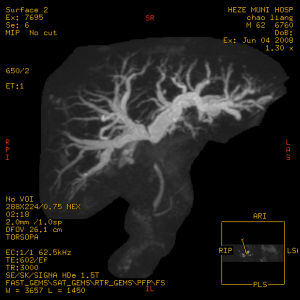

②逆行膽道造影、PTC、ERCP,可顯示狹窄部位、形態及範圍。膽管未顯影,不能除外膽管狹窄。有時靜脈膽道造影,也可顯示病變膽管。③B型超聲可示狹窄近端膽管擴張、或(和)結石的聲像圖。

4、“T”管逆行造影、靜脈膽道造影、PTC、ERCP等檢查,可顯示狹窄部位及形態。可行膽腸引流者,用對比造影法有助於診斷。